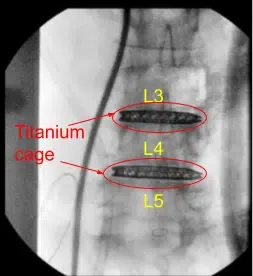

Radiografía postoperatoria

Radiografía intraoperatoria

Las radiografías AP y laterales indicaron una excelente posición en la jaula, restauración de la lordosis y descompresión indirecta en todo el sistema. En consecuencia, la jaula L3-L4 se liberó del insertador de jaula. La zona fue abundantemente irrigada con solución fisiológica impregnada con antibióticos y llena de producto de matriz hemostática Surgiflo.

Vista sagital postoperatoria por rayos X